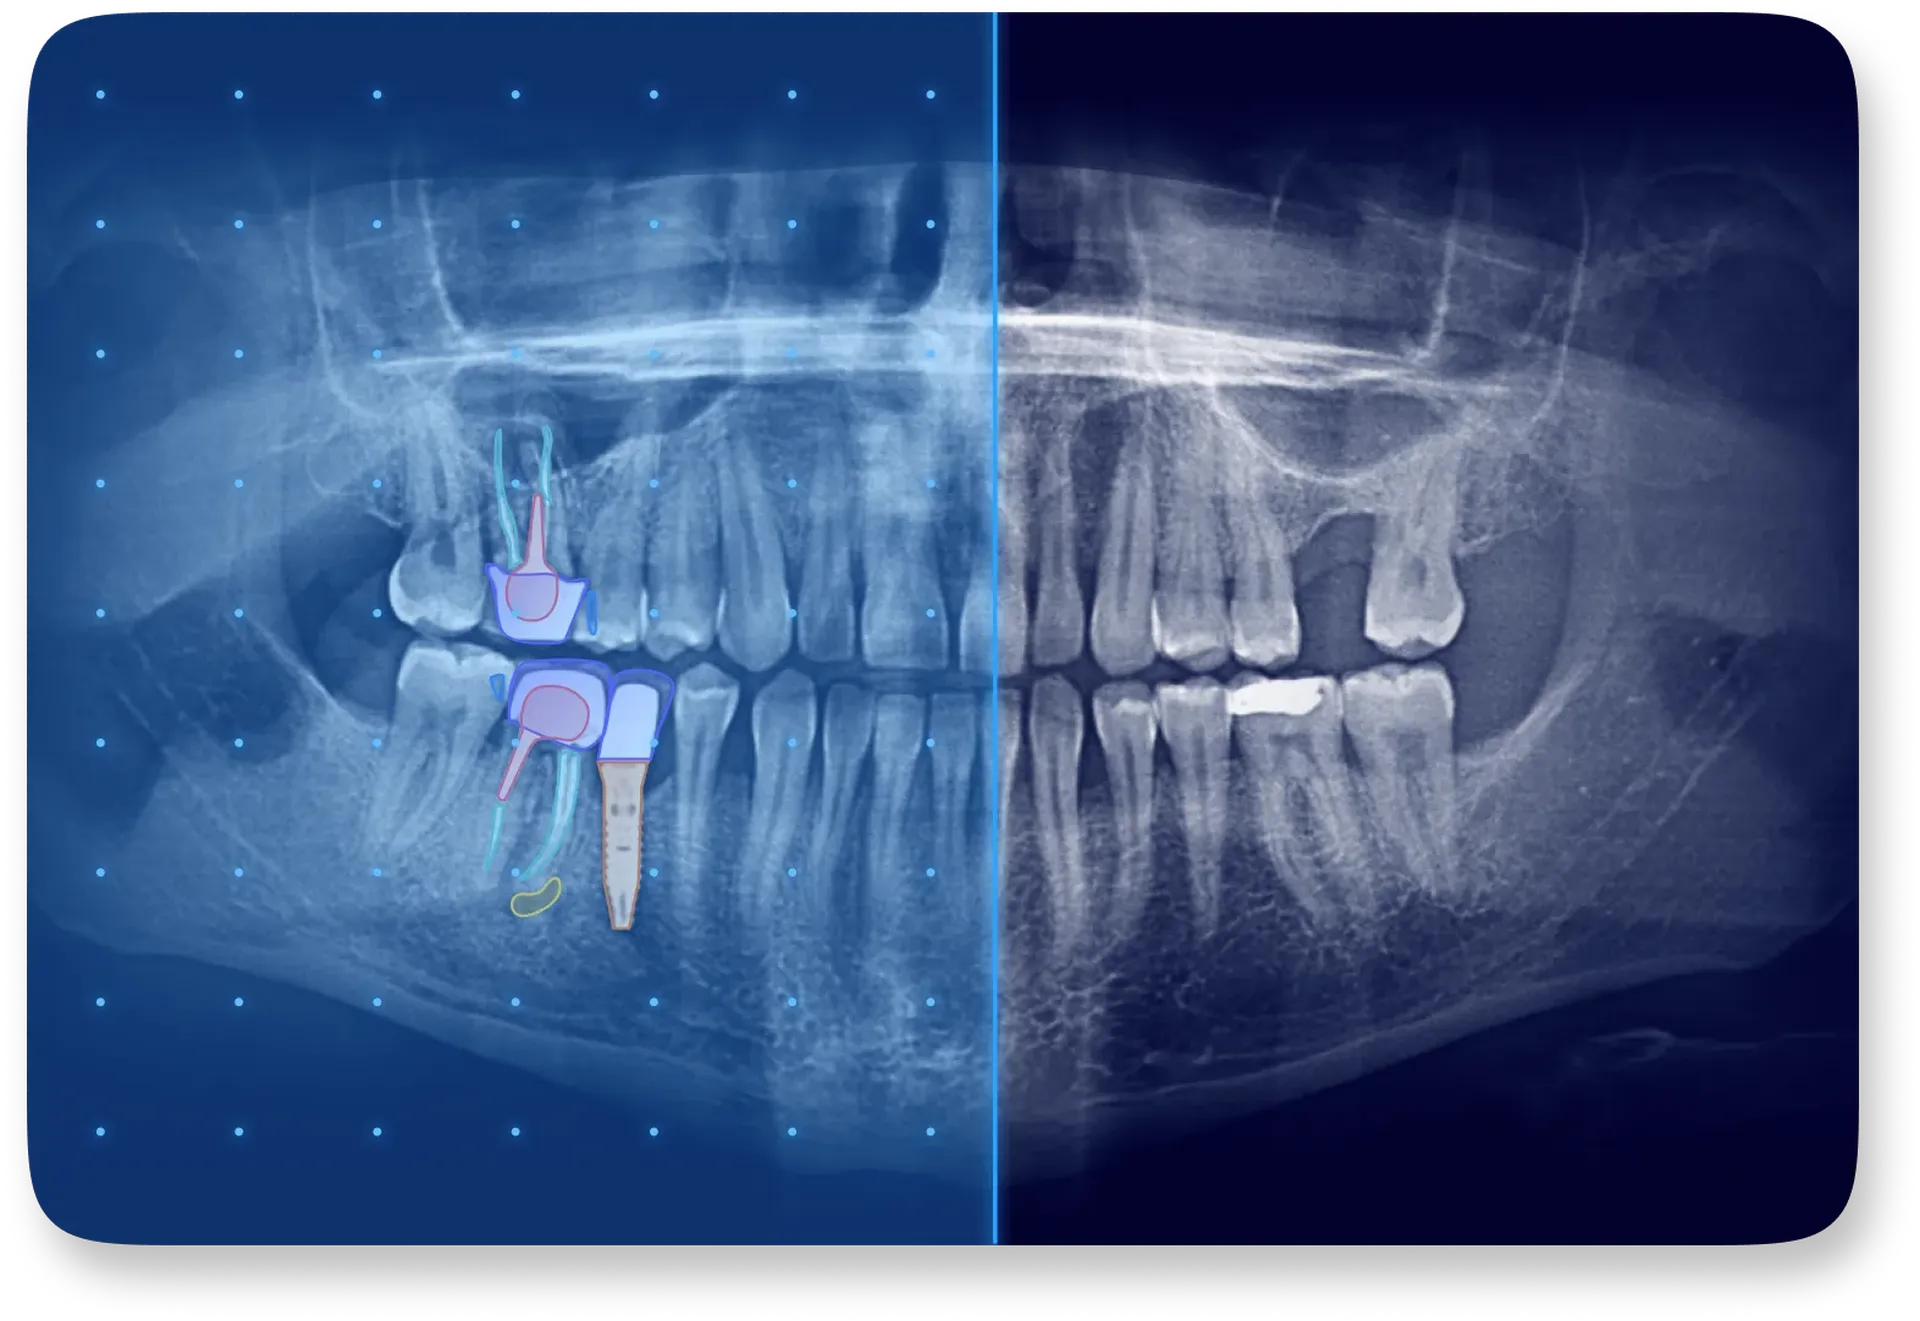

L’intelligence artificielle (IA) s’impose progressivement dans la dentisterie, transformant tant le diagnostic que la relation patient-praticien. En imagerie par exemple, l’IA permet de détecter automatiquement des anomalies sur des radiographies panoramiques ou CBCT, améliorant la sensibilité et la spécificité des diagnostics, limitant ainsi la variabilité des interprétations entre praticiens. Elle contribue aussi à fluidifier le pilotage du cabinet dentaire en analysant les données patients, les paramètres d’activité et les devis, ce qui offre une vision anticipée de la productivité et de la rentabilité.

La communication patient est un autre champ clé : grâce à des outils visuels basés sur l’IA, les éléments pathologiques sont mis en évidence par des codes couleur, des schémas explicatifs et des rapports pédagogiques. Résultat : les patients comprennent mieux leur situation, adhèrent davantage aux traitements proposés et sont ainsi plus engagés. Cela se traduit par une augmentation notable du taux d’acceptation des plans de traitement.

Allisone est une solution logicielle basée sur l’intelligence artificielle conçue pour accompagner les praticiens dentaires dans leur communication avec les patients, leur planification et leur diagnostic. Grâce à une interface intuitive, elle permet de mettre en évidence les repères radiographiques à l’aide de codes couleur et d’illustrations pédagogiques, facilitant ainsi la compréhension des images par les patients et renforçant leur confiance dans les soins proposés.